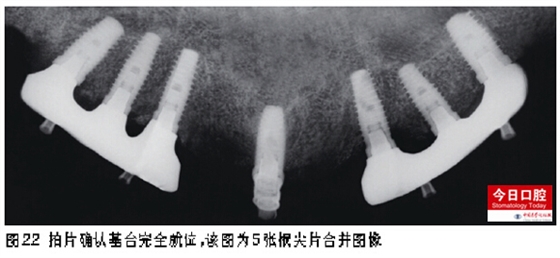

一期植入4顆種植體后,CBCT復(fù)查植入的情況。請注意13的位置由于拔牙創(chuàng)的影響無法應(yīng)用導(dǎo)板,而且拔牙創(chuàng)側(cè)壁也影響了種植位置。先鋒鉆導(dǎo)板的特點(diǎn)是植入點(diǎn)進(jìn)入位置較準(zhǔn)確,但對后序步驟的指導(dǎo)作用尚不足,所以我們的經(jīng)驗(yàn)是使用全程多級套筒導(dǎo)板效果較先鋒鉆導(dǎo)板更佳(圖5)。中切牙位點(diǎn)水平向骨量有限,將切牙管內(nèi)軟組織掏出后填入了Bio-Oss(圖6)。最終的植入型號自右上至左上依次為Biomet3I IFNT513、IFNT411、IFNT411、IFNT413、IFNT413、IFNT413、IFNT511。種植體邊緣均設(shè)為骨緣下0.5mm,安裝封閉螺絲后嚴(yán)密縫合切口。植入扭力矩均大于35Ncm。上尖牙拔牙窩與種植體間隙之間放置Bio-Oss骨粉并覆蓋BioGid生物膜。術(shù)后半年開始修復(fù),治療過程詳見圖7~25。